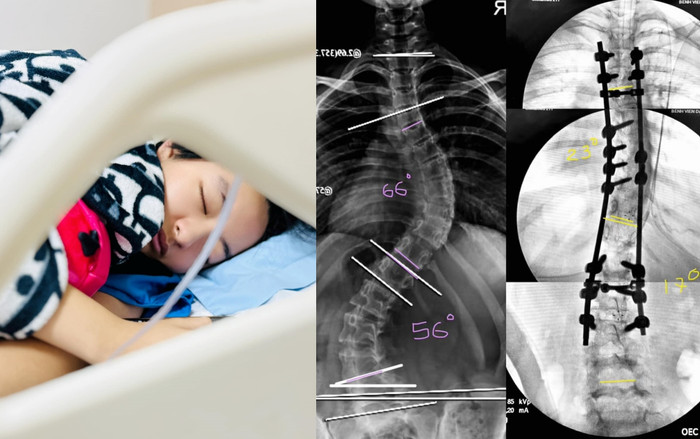

Được biết, ca phẫu thuật cột sống của con gái Thúy Hằng kéo dài 6 tiếng, với phương pháp mổ hạn chế xâm lấn. Nói về tình trạng của con gái, Thúy Hằng chia sẻ: "Con hồi phục nhanh 1 cách thần kỳ, sau 2 tuần đã theo cả nhà đi Phú Quốc luôn được rồi, còn bây giờ sau hơn 1 tháng sắp chạy nhảy khắp nơi rồi".  Siêu mẫu Thúy Hằng không giấu tự hào khi con gái không chỉ hồi phục tốt mà còn mạnh mẽ, nhanh chóng trở lại cuộc sống bình thường. Cô cũng vui vẻ tiết lộ bé Bông hiện tại đã trở thành "Iron girl" với 2 nẹp Titan và 16 vít trong cơ thể.

Đi kèm với bài viết, siêu mẫu Thúy Hằng còn đăng tải hình ảnh về tình trạng cột sống của con gái trước và sau khi phẫu thuật. Những bức ảnh này khiến cư dân mạng không khỏi xúc động, rất nhiều lời chúc và động viên đã được gửi đến con gái Thúy Hằng.

Kết quả trước và sau phẫu thuật cột sống của con gái Thúy Hằng.